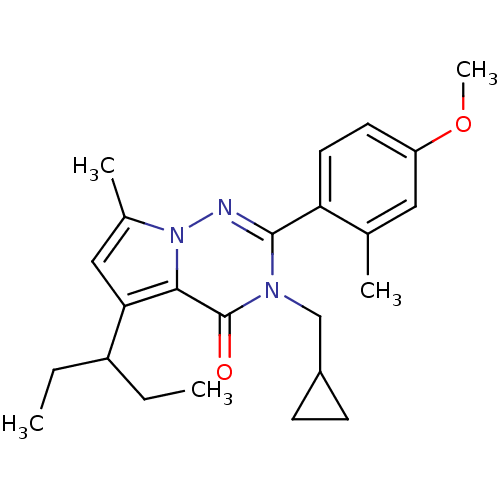

TargetCorticotropin-releasing factor receptor 1(Homo sapiens (Human))

Dupont Pharmaceuticals

Curated by ChEMBL

Dupont Pharmaceuticals

Curated by ChEMBL

Affinity DataEC50: 0.300nMAssay Description:Antagonist activity at human CRF1 receptor expressed in CHO-K1 cells assessed as CRF-stimulated cAMP accumulation by enzyme immunoassayMore data for this Ligand-Target Pair

Affinity DataEC50: 0.420nMAssay Description:Antagonist activity at CRF-R1 in mouse AtT-20 cells assessed as inhibition of human CRF induced cAMP accumulation after 30 mins by radioimmunoassayMore data for this Ligand-Target Pair

Affinity DataEC50: 0.440nMAssay Description:Antagonist activity at CRF-R1 in mouse AtT-20 cells assessed as inhibition of human CRF induced cAMP accumulation after 30 mins by radioimmunoassayMore data for this Ligand-Target Pair

Affinity DataEC50: 0.450nMAssay Description:Antagonist activity at CRF-R1 in mouse AtT-20 cells assessed as inhibition of human CRF induced cAMP accumulation after 30 mins by radioimmunoassayMore data for this Ligand-Target Pair